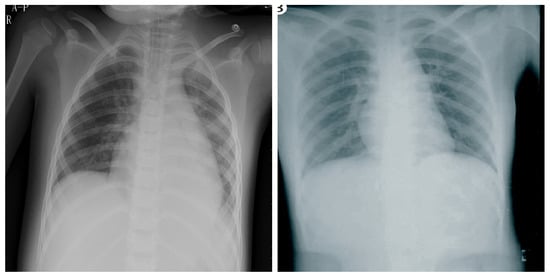

3.6. Montgomery County X-ray

3.7. Shenzhen Hospital X-ray